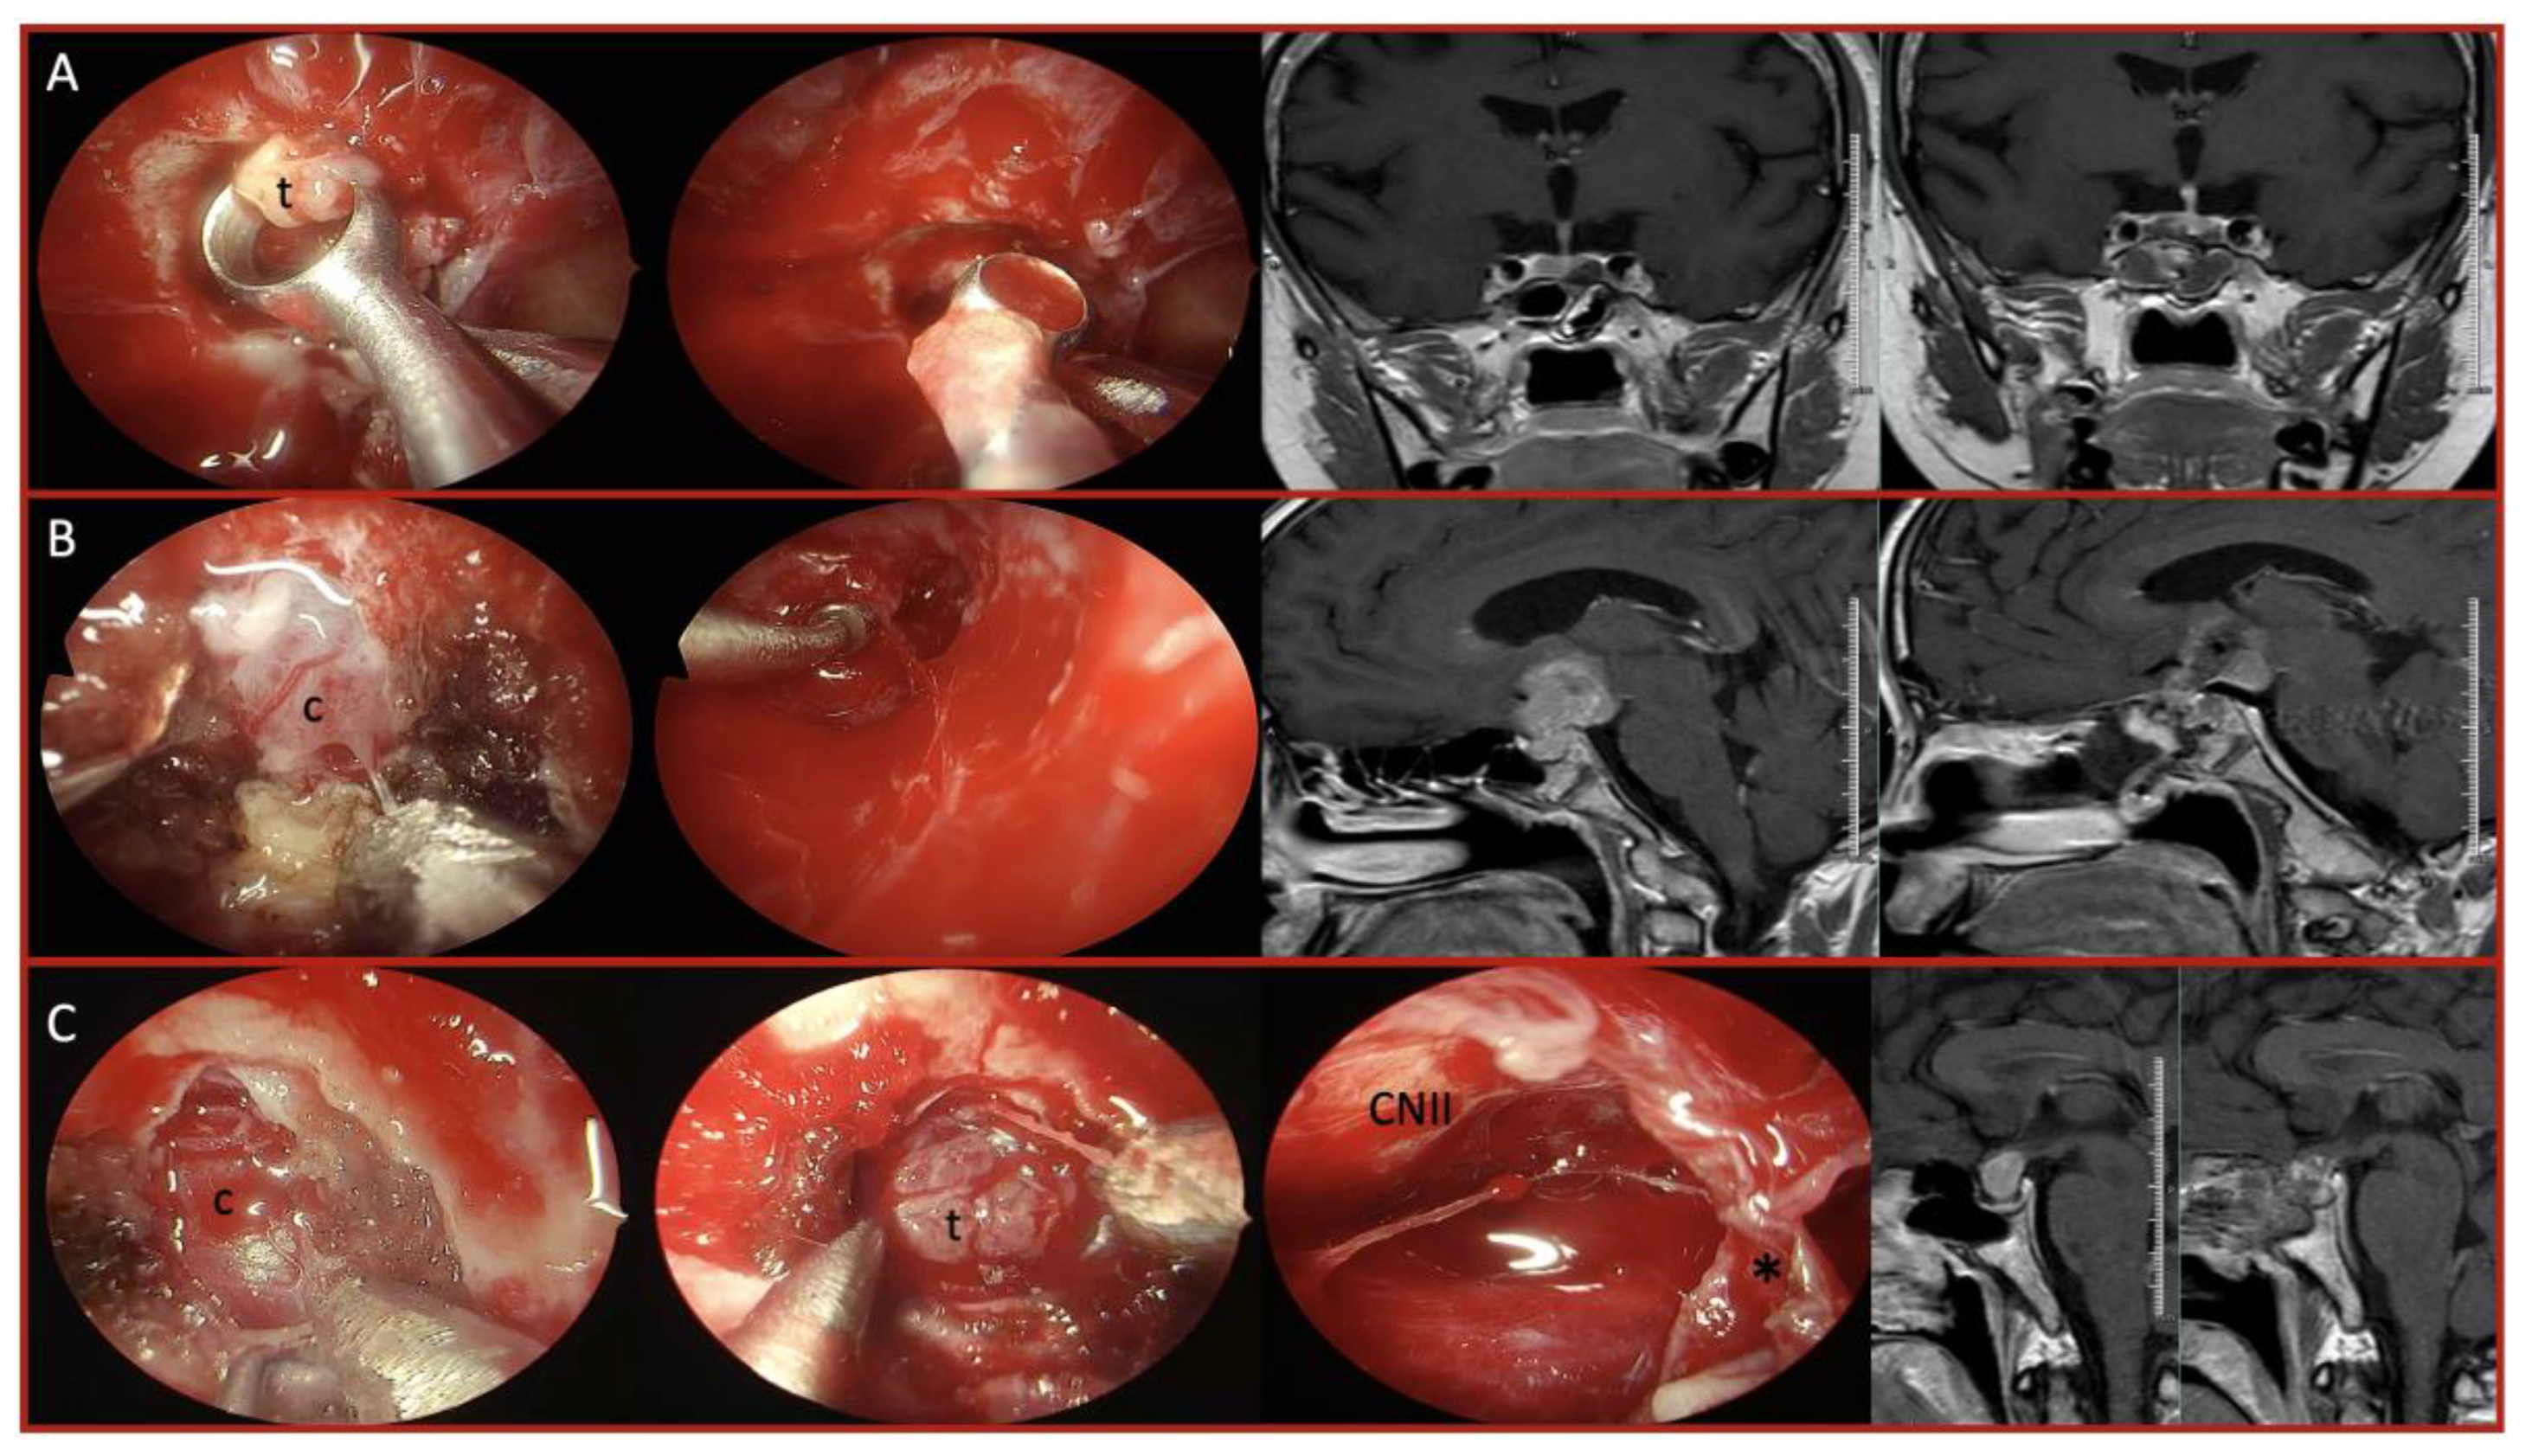

Background: Endoscopic endonasal approach (EEA) has become a well- established approach for skull base pathologies, providing a minimally invasive corridor to access various lesions. While the technique has been extensively studied for common skull base tumors, data on extremely rare pathologies remain limited. Our study aims to present our experience with rare skull base lesions managed via the endoscopic endonasal approach, highlighting the challenges associated with preoperative diagnosis, intraoperative decision-making, and surgical strategy modifications. Methods: A retrospective analysis was conducted on patients who underwent endoscopic endonasal surgery at the tertiary center up to January 2025. Among 6,225 endoscopic endonasal procedures performed, 41 patients with exceptionally rare skull base pathologies were identified. Each tumor type was separately evaluated for differences in resection rates, complication rates, and recurrence patterns. Results: These included 6 pituitary pituicytomas, 5 plasmacytomas, 5 xanthogranulomas, 4 granular cell tumors, 3 giant cell tumors and others. Gross total resection was achieved in 68% of cases, with subtotal resection in vascular or malignant tumors. Intraoperative challenges included unexpected vascularity and fibrotic adhesions. Postoperative CSF leakage occurred in 7%, and recurrence was observed in 17%, mostly in malignant or partially resected tumors. No intraoperative mortality was recorded. Tailored adjuvant treatments ensured durable disease control in most patients. Conclusions: Even in highly experienced centers, rare skull base pathologies pose unique diagnostic and surgical challenges. The discrepancy between preoperative and intraoperative findings often necessitates real-time strategic adaptations. In these rare cases, for optimizing patient outcomes requires a comprehensive understanding of skull base anatomy, flexibility in surgical planning, readiness for sudden strategy modifications, and a multidisciplinary approach.

| Tumor Type | No. of Cases | Consistency / Vascularity | Extent of Resection | Adjuvant Therapy / Recurrence |

|---|---|---|---|---|

| Pituicytoma | 6 | Firm, highly vascular capsule | GTR/STR (5/1) |

No recurrence, no adjuvant |

| Plasmacytoma | 5 | Soft, moderately vascular | GTR/STR (3/2) |

RT + chemo; 2 recurrences |

| Xanthogranuloma | 5 | Fibrotic, adherent | GTR | No recurrence |

| Granular cell tumor | 4 | Soft intense | GTR | Gamma Knife (case-based) |

| Giant cell tumor | 3 | Highly vascular | GTR Pre-operative embolization |

Denosumab Fully controlled |

| Germinoma | 2 | Soft, Vascular capsule | STR | Chemo + RT; 1 recurrence |

| HPC | 2 | Hypervascular | STR | RT; 1 recurrence |

| LCH | 2 | Firm, fibrotic | GTR/STR (1/1) |

Systemic chemo; stable |

| Malignant epithelial | 2 | Adherent, fibrotic | STR | 1 Recurrence |

| Spindle cell oncocytoma | 2 | Firm, vascular | GTR/ STR 1/1 |

1 Gamma Knife |

| Others (each 1) | 10 | Varied | Varied | Case-specific |